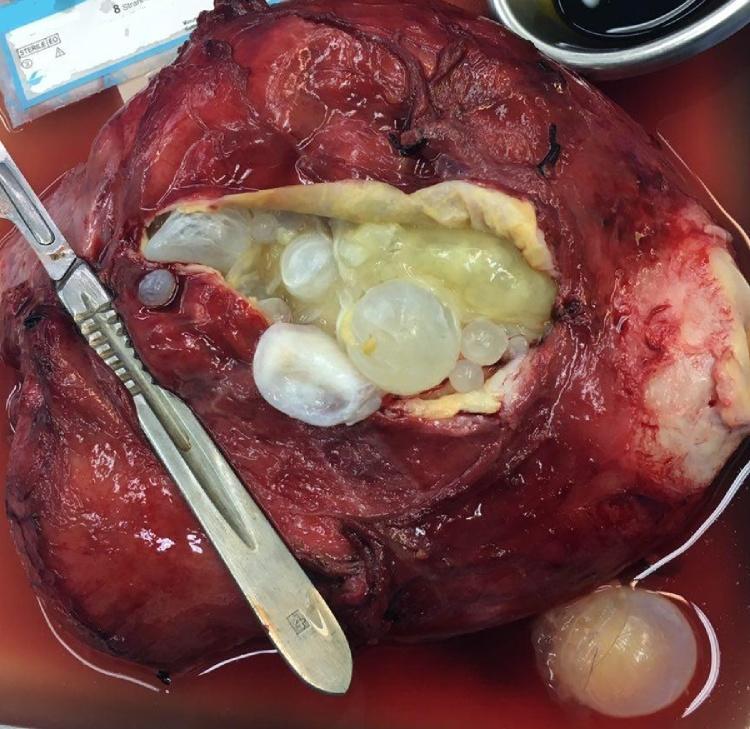

PRESENTATION OF CASE

We here report a case of primary uterus hydatid cyst that we had to remove her uterine on left ovary and fallopian tube. Generalized toxic shock and infection due to cyst rupture or organ dysfunction due to invasion (like our patient) or pressure of cyst are complications of this cyst.

病例介绍

我们在此报告一例原发性子宫包虫囊肿病例,我们不得不切除其左侧卵巢和输卵管的子宫。囊肿破裂导致的全身性中毒性休克和感染,或因囊肿侵袭(如我们的患者)或压迫导致的器官功能障碍,是这种囊肿的并发症。